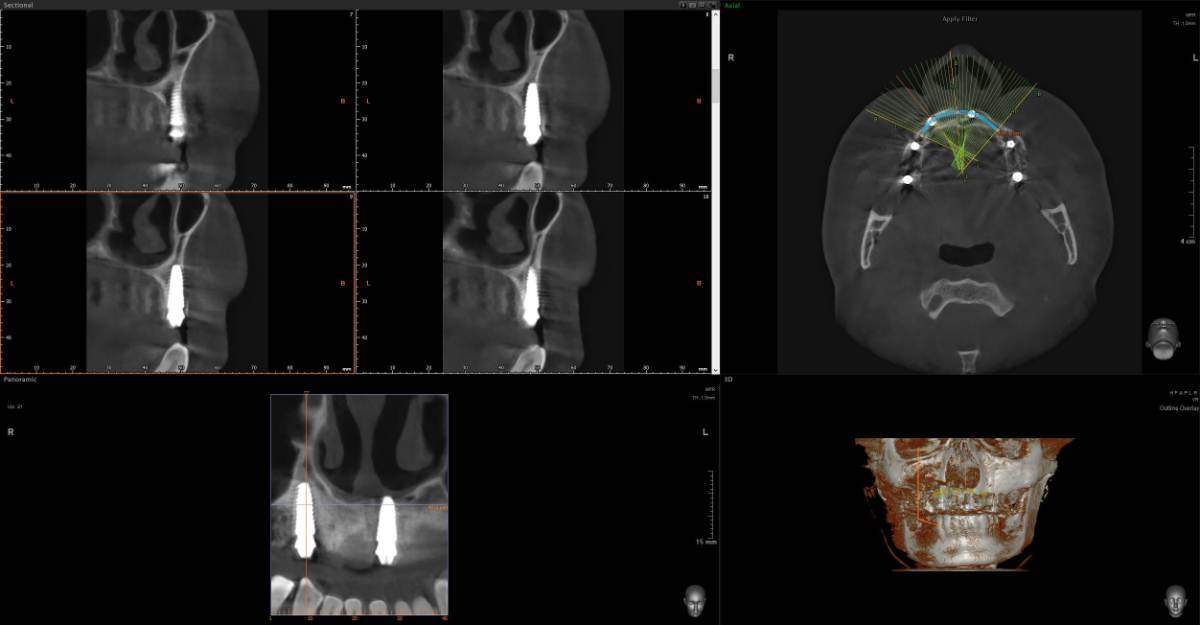

Всем привет, коллеги! 14 лет, терапевты ставят трещину по КТ (снимков до, к сожалению нет, косяк, каюсь). чуть сепарировав зуб и глянув на зуб под отлетевшим куском пломбы трещина "подтвердилась". Кейс на фото. Из интересного - маленький реколл в 1.5 года и спокойное перемещение зуба брекетами!

@сирена вот и завтра наступило) прощу прощения, что так долго, всё из головы вылетало на работе посмотреть. Пересадили в конце мая, к ортодонтии подключили в начале сентября ~3.5 месяца прошло с пересадки на тот момент.